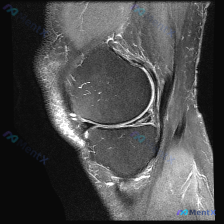

给大家分享一个很有启发的膝关节MRI读片病例,临床关注点是半月板异常,读完片发现其实核心问题不在这儿,整理一下完整分析思路。 病例影像基本信息 这是一份膝关节矢状位T2加权MRI(压脂序列),我们先整理所有客观发现: 1. 关节内结构:半月板形态完整,呈典型低信号三角表现,未见贯穿性高信号,边缘光滑...

看到一份很有启发的膝关节MRI病例,初始提示是「半月板异常」,但读片后的发现和一开始的方向完全不一样,整理一下完整分析思路跟大家分享。 一、病例影像基础信息 这是膝关节MRI矢状位T2加权图像,我们先整理所有客观发现: 1. 骨骼关节:股骨远端、胫骨近端、髌骨骨皮质完整,无明显骨折或骨质破坏,髌骨与...

病例读片分享:临床怀疑半月板异常,MRI却只看到髌周病变 基本影像信息 提供的影像为膝盖MRI-T2序列矢状位,切面位于膝关节前部髌股关节区域,图像存在一定截断伪影,未显示后交叉韧带及大部分后侧软组织结构。 影像核心发现 整理一下客观观察到的异常: 1. 髌前皮下软组织水肿:髌骨前方及皮下组织层可见...

看到这份有意思的病例,主诉是提示半月板异常的膝关节MRI,整理了完整的读片思路和分析,分享给大家。 一、影像基础信息 这是一幅膝关节MRI T2加权矢状位图像,我们先确认基础信息: - 成像序列符合T2WI特征:液体高信号、软骨中等信号、脂肪低信号、骨皮质及韧带低信号 - 切面展示膝关节前部结构:髌...